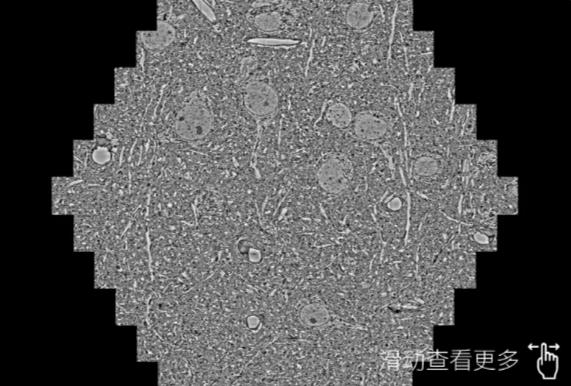

鼠脑切片。左图使用巴音郭楞蔡司巴音郭楞扫描电镜MultiSEM706对165μmx143pm面积区域成像,耗时仅需1.5秒。右图为鼠脑切片中30μm区域放大效果。样品由芝加哥大学B.Kasthuri提供。

使用蔡司高速巴音郭楞扫描电镜MultiSEM对1mm²人脑皮层组织进行高分辨成像,并对其中的各种细胞结构进行三维重构分析。左图展示了2x3mm²组织平面中锥体神经元的三维重构效果。右图显示了局部体积神经元三维重构。图像由哈佛大学chtman实验室提供,渲染图由D. Berger 制作。